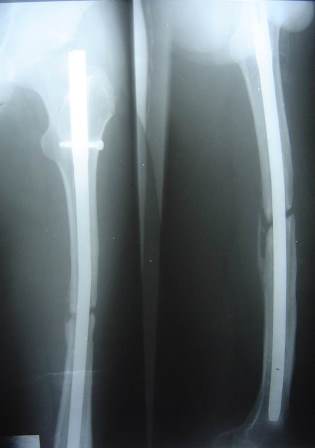

19-year-old male had fracture of femur which was treated by open IM nailing with aseptic non-union for 2 years where stiff knee arthroscopy and knee manipulation were done.

A few months later the patient presented with 2 nail breaks.